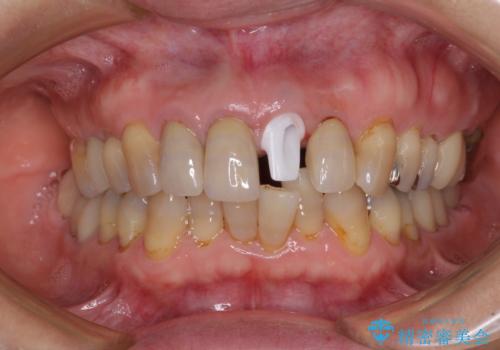

1. 折れてしまった前歯 インプラントによる補綴治療の治療前

1.